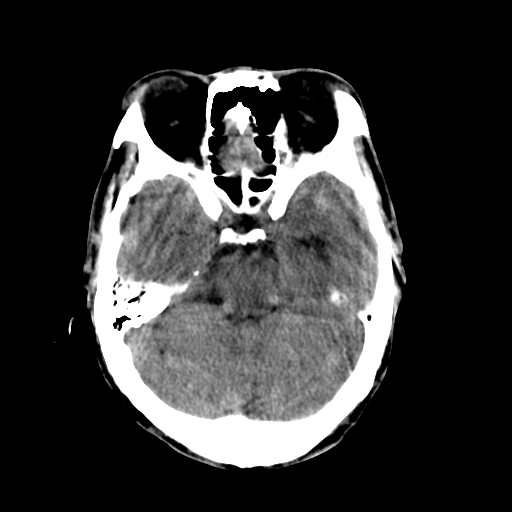

标题: CT17002:M48Y,血管畸形,血管瘤,请鉴赏! [打印本页]

男48y,头痛多年,加重一天!

典型的血管畸形---avm  -----右侧枕顶叶及侧脑室三角区等高混杂密度影夹杂少许低密影显示,无明显水肿,增强可见明显的供血动脉与引流静脉显示